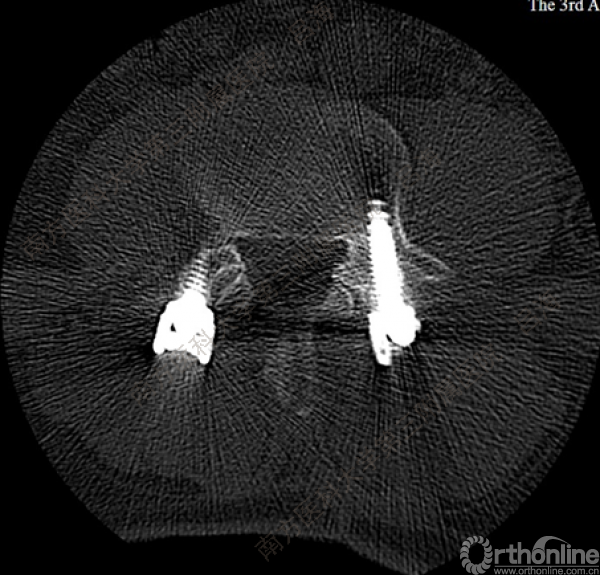

随着社会老龄化进程加快,胸腰椎退行性病变的治疗已经成为脊柱学术界的一个热点话题。MIS-TLIF手术可以治疗多种不同的胸腰椎退行性疾病,南方医科大学第三附属医院吕海教授结合病例为我们一一展示了该术式在治疗不同胸腰椎疾病时的具体手术过程。